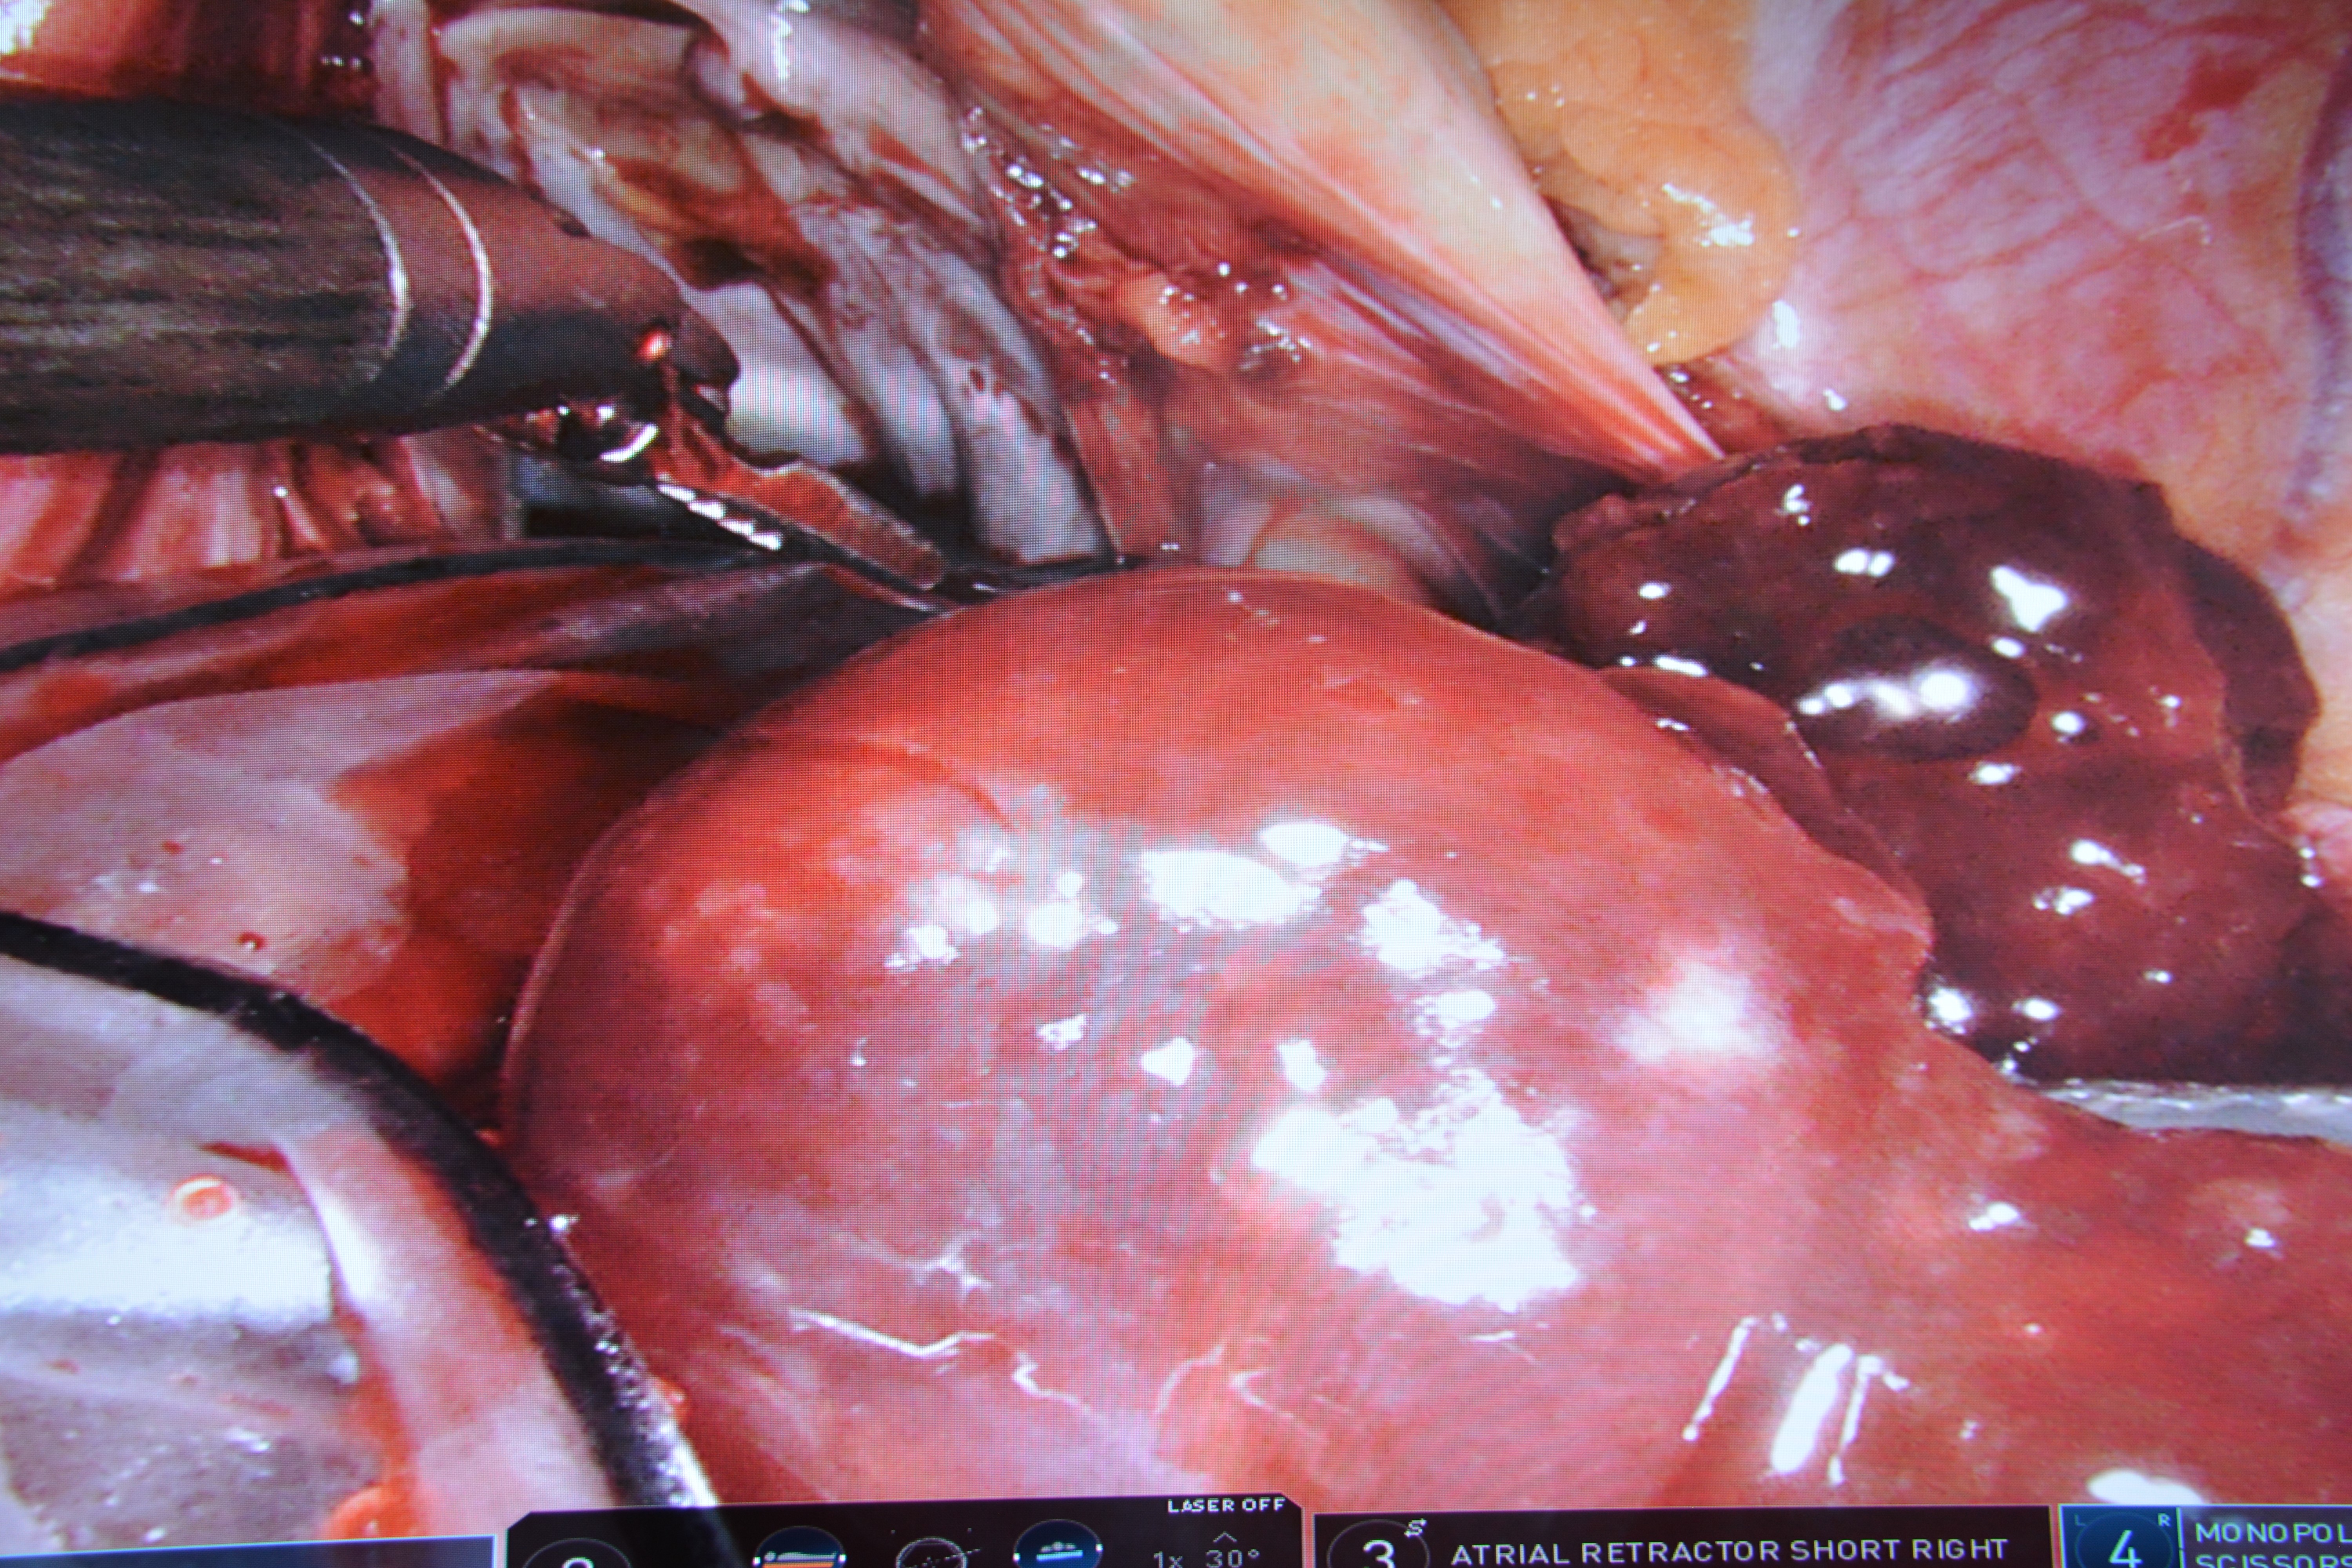

Dnia 09.08.2021r w Centralnym Szpitalu Klinicznym MSWiA, prof. dr hab. n. med. Piotr Suwalski wraz zespołem usunął guz serca i zaszył ubytek w przegrodzie serca za pomocą robota da Vinci. Była to pierwsza taka operacja w Polsce.